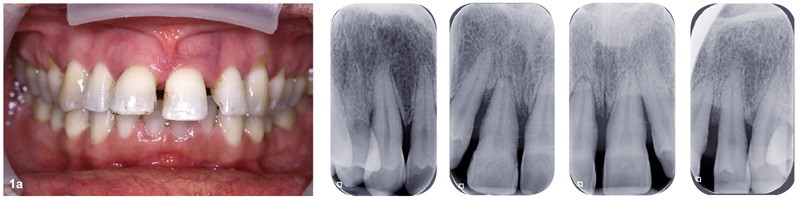

Bien souvent, dans les formes sévères, la diminution du boîtier osseux entraîne la migration et le déplacement de dents et notamment dans le secteur antérieur. Ces migrations ont un aspect disgracieux qui amène bon nombre de patients à consulter un orthodontiste pour corriger ces malpositions et retrouver à la fois une esthétique du sourire plus agréable et une fonction masticatrice plus efficace. Cependant, l’origine de ces migrations tient à l’inflammation du parodonte se traduisant par une plus grande laxité ligamentaire et une destruction du boîtier osseux. Dans certains cas, une surcharge occlusale aggrave encore le déplacement. Le traitement de l’inflammation par une thérapeutique initiale parodontale diminue la migration mais souvent, ne suffit pas à retrouver un positionnement correct (fig. 1). Il est alors nécessaire de mettre en œuvre une prise en charge orthodontique.